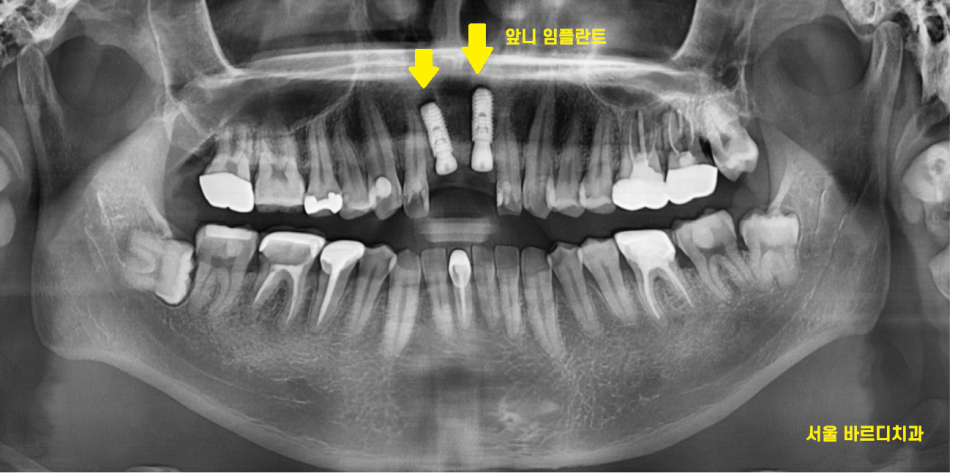

큰 x-ray로 확인을 해보니..

여지없이 신경치료가 되어 있는 상황

작은 x-ray로 한 번 더 확인해 보았습니다.

2/3 이상 머리가 없어졌네요..

앞니 부러짐 치료의 방향을 결정할 때에는

남아있는 치아의 양이 중요합니다.

살릴 수 있을지 없을지

예후를 결정하는

key point이죠!!

잇몸뼈에 뿌리만 박혀있는 수준이라

발치 후 임플란트 계획을

잡아드렸습니다.